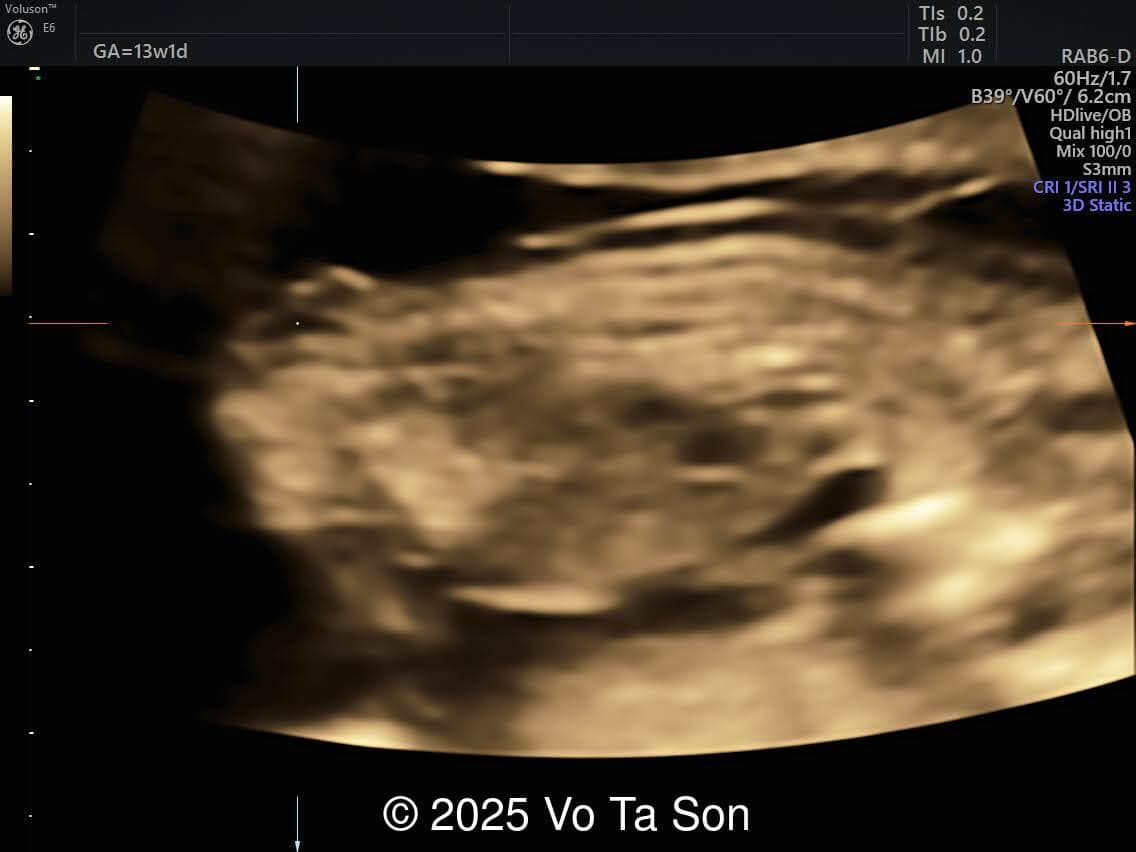

A 13-week pregnant woman underwent routine prenatal screening. The non-invasive prenatal test (NIPT) showed low risk for common aneuploidies (trisomy 21, 18, and 13). However, first-trimester anomaly scan revealed the following significant fetal abnormalities:

- Cystic-appearing placenta, suggestive of partial molar changes

Karyotype results revealed triploidy with a 69,XXY chromosomal complement, consistent with diandric triploidy (paternal origin). This finding correlated well with the ultrasound abnormalities, particularly the cystic placenta and multiple fetal structural defects.